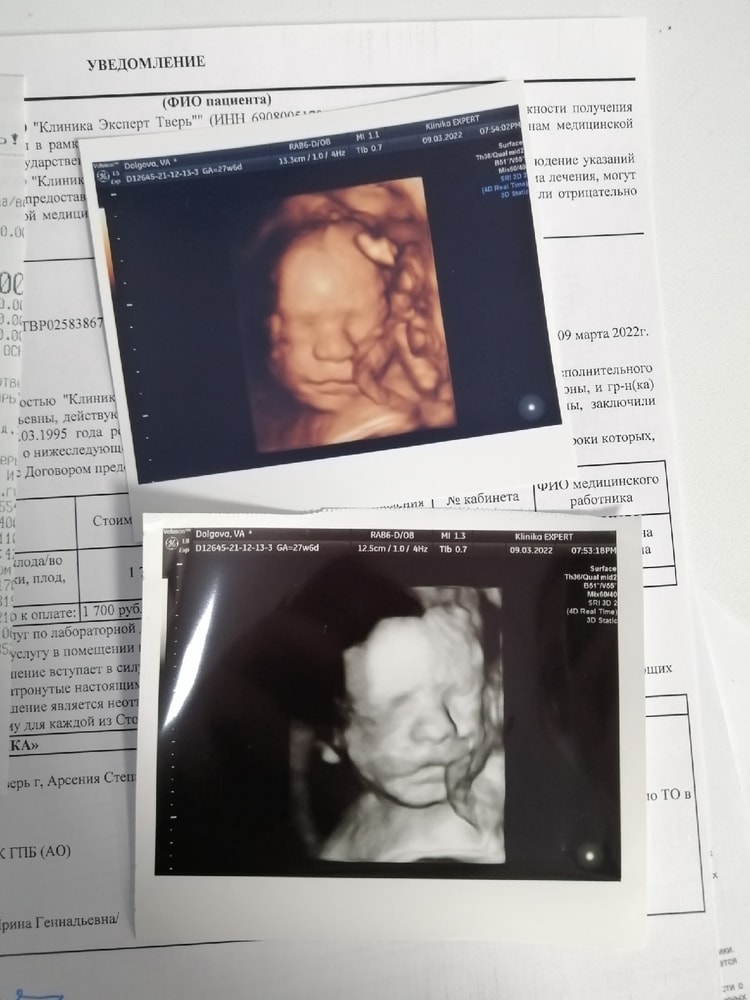

Олеся, вот сын. Мне кажется, что к 25 недельке уже можно было бы😅 Изображение

11.10.2025